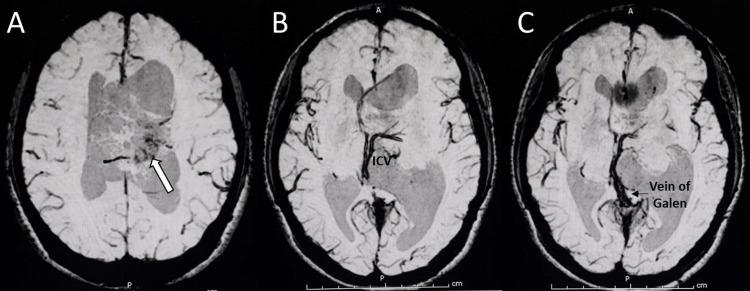

Central neurocytoma (CN) is a rare intraventricular tumor. The common presenting symptoms of CN are headache, vomiting, and visual disturbance, which results from increased intracranial pressure. This report presents a case of CN with unusual clinical presentations. A 25-year-old female with CN presented with a one-day history of unilateral headache, ipsilateral periorbital pain, multifocal paresthesias, and vomiting. Magnetic resonance images showed an intraventricular mass with a soap-bubble appearance and numerous cystic areas typical for CN, causing obstructive hydrocephalus and a midline shift. After one night of rest, her headache, periorbital pain, and paresthesias disappeared. It is possible that the tumor could be mobile with regard to the patient's head position, causing occasional obstruction of the foramen of Monro. Due to the tumor size, which was larger than 4 centimeters, the surgical approach with either gross tumor resection or subtotal resection plus adjuvant radiotherapy should be carefully considered.

中枢神经细胞瘤(CN)是一种罕见的脑室内肿瘤。CN的常见症状为头痛、呕吐和视觉障碍,这些症状由颅内压升高引起。本报告介绍了一例具有不寻常临床表现的CN病例。一名患有CN的25岁女性,有一天的单侧头痛、同侧眶周疼痛、多灶性感觉异常和呕吐病史。磁共振成像显示脑室内有一个呈肥皂泡样外观且有许多典型CN囊性区域的肿块,导致梗阻性脑积水和中线移位。经过一晚休息后,她的头痛、眶周疼痛和感觉异常消失了。肿瘤可能会随着患者头部位置移动,偶尔阻塞Monro孔。鉴于肿瘤大小超过4厘米,应仔细考虑采用肿瘤全切或次全切除加辅助放疗的手术方法。